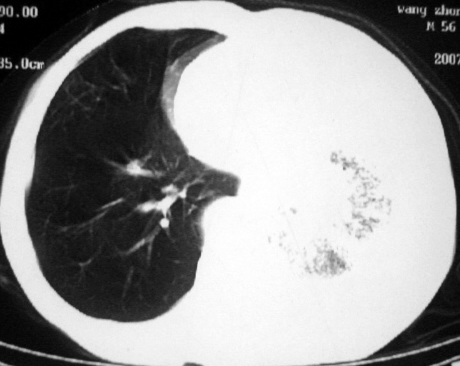

男,54岁,咳嗽,气喘半年,胸痛一月.

血性胸水

左侧胸腔积液 斜裂积液 心包积液 左肺不张 考虑左肺ca并胸膜心包转移。

支持左肺下叶中心型肺癌(累及舌叶)伴阻塞性肺炎、膨胀不全、胸腔积液、心包少量积液。

1.左肺下叶中心性肺癌伴阻塞性肺炎,肺不张.

2.左侧胸腔积液,心包积液